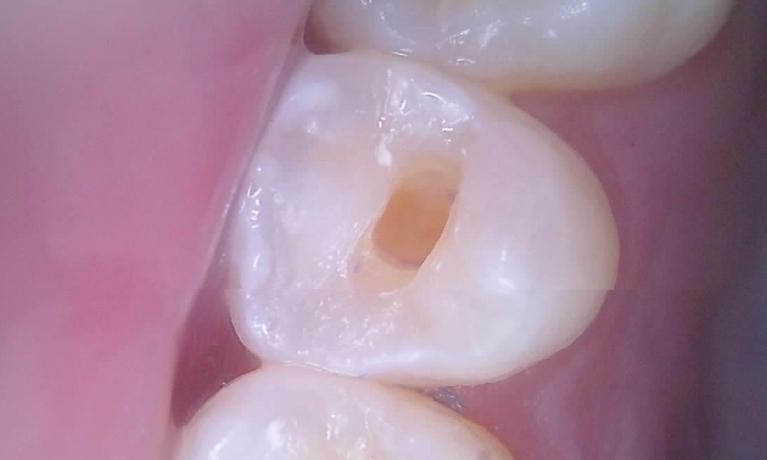

We take great pride in the services we perform in our office. We always try to not only meet your expectations, but we also try to exceed them. There are many types of services that we perform in our office, as well as others that we perform in coordination with highly skilled specialists. We have compiled a few examples of the treatments that we have performed. We are proud to say that these are the usual results our patients expect to see.

The photos are not retouched, nor are they taken by a professional photographer. These are just the routine treatment photos that we take and the results that we see every day. They are by no means a comprehensive catalog of the procedures that we perform. They are just a small sample of some of the results you can expect when you seek treatment in our office.